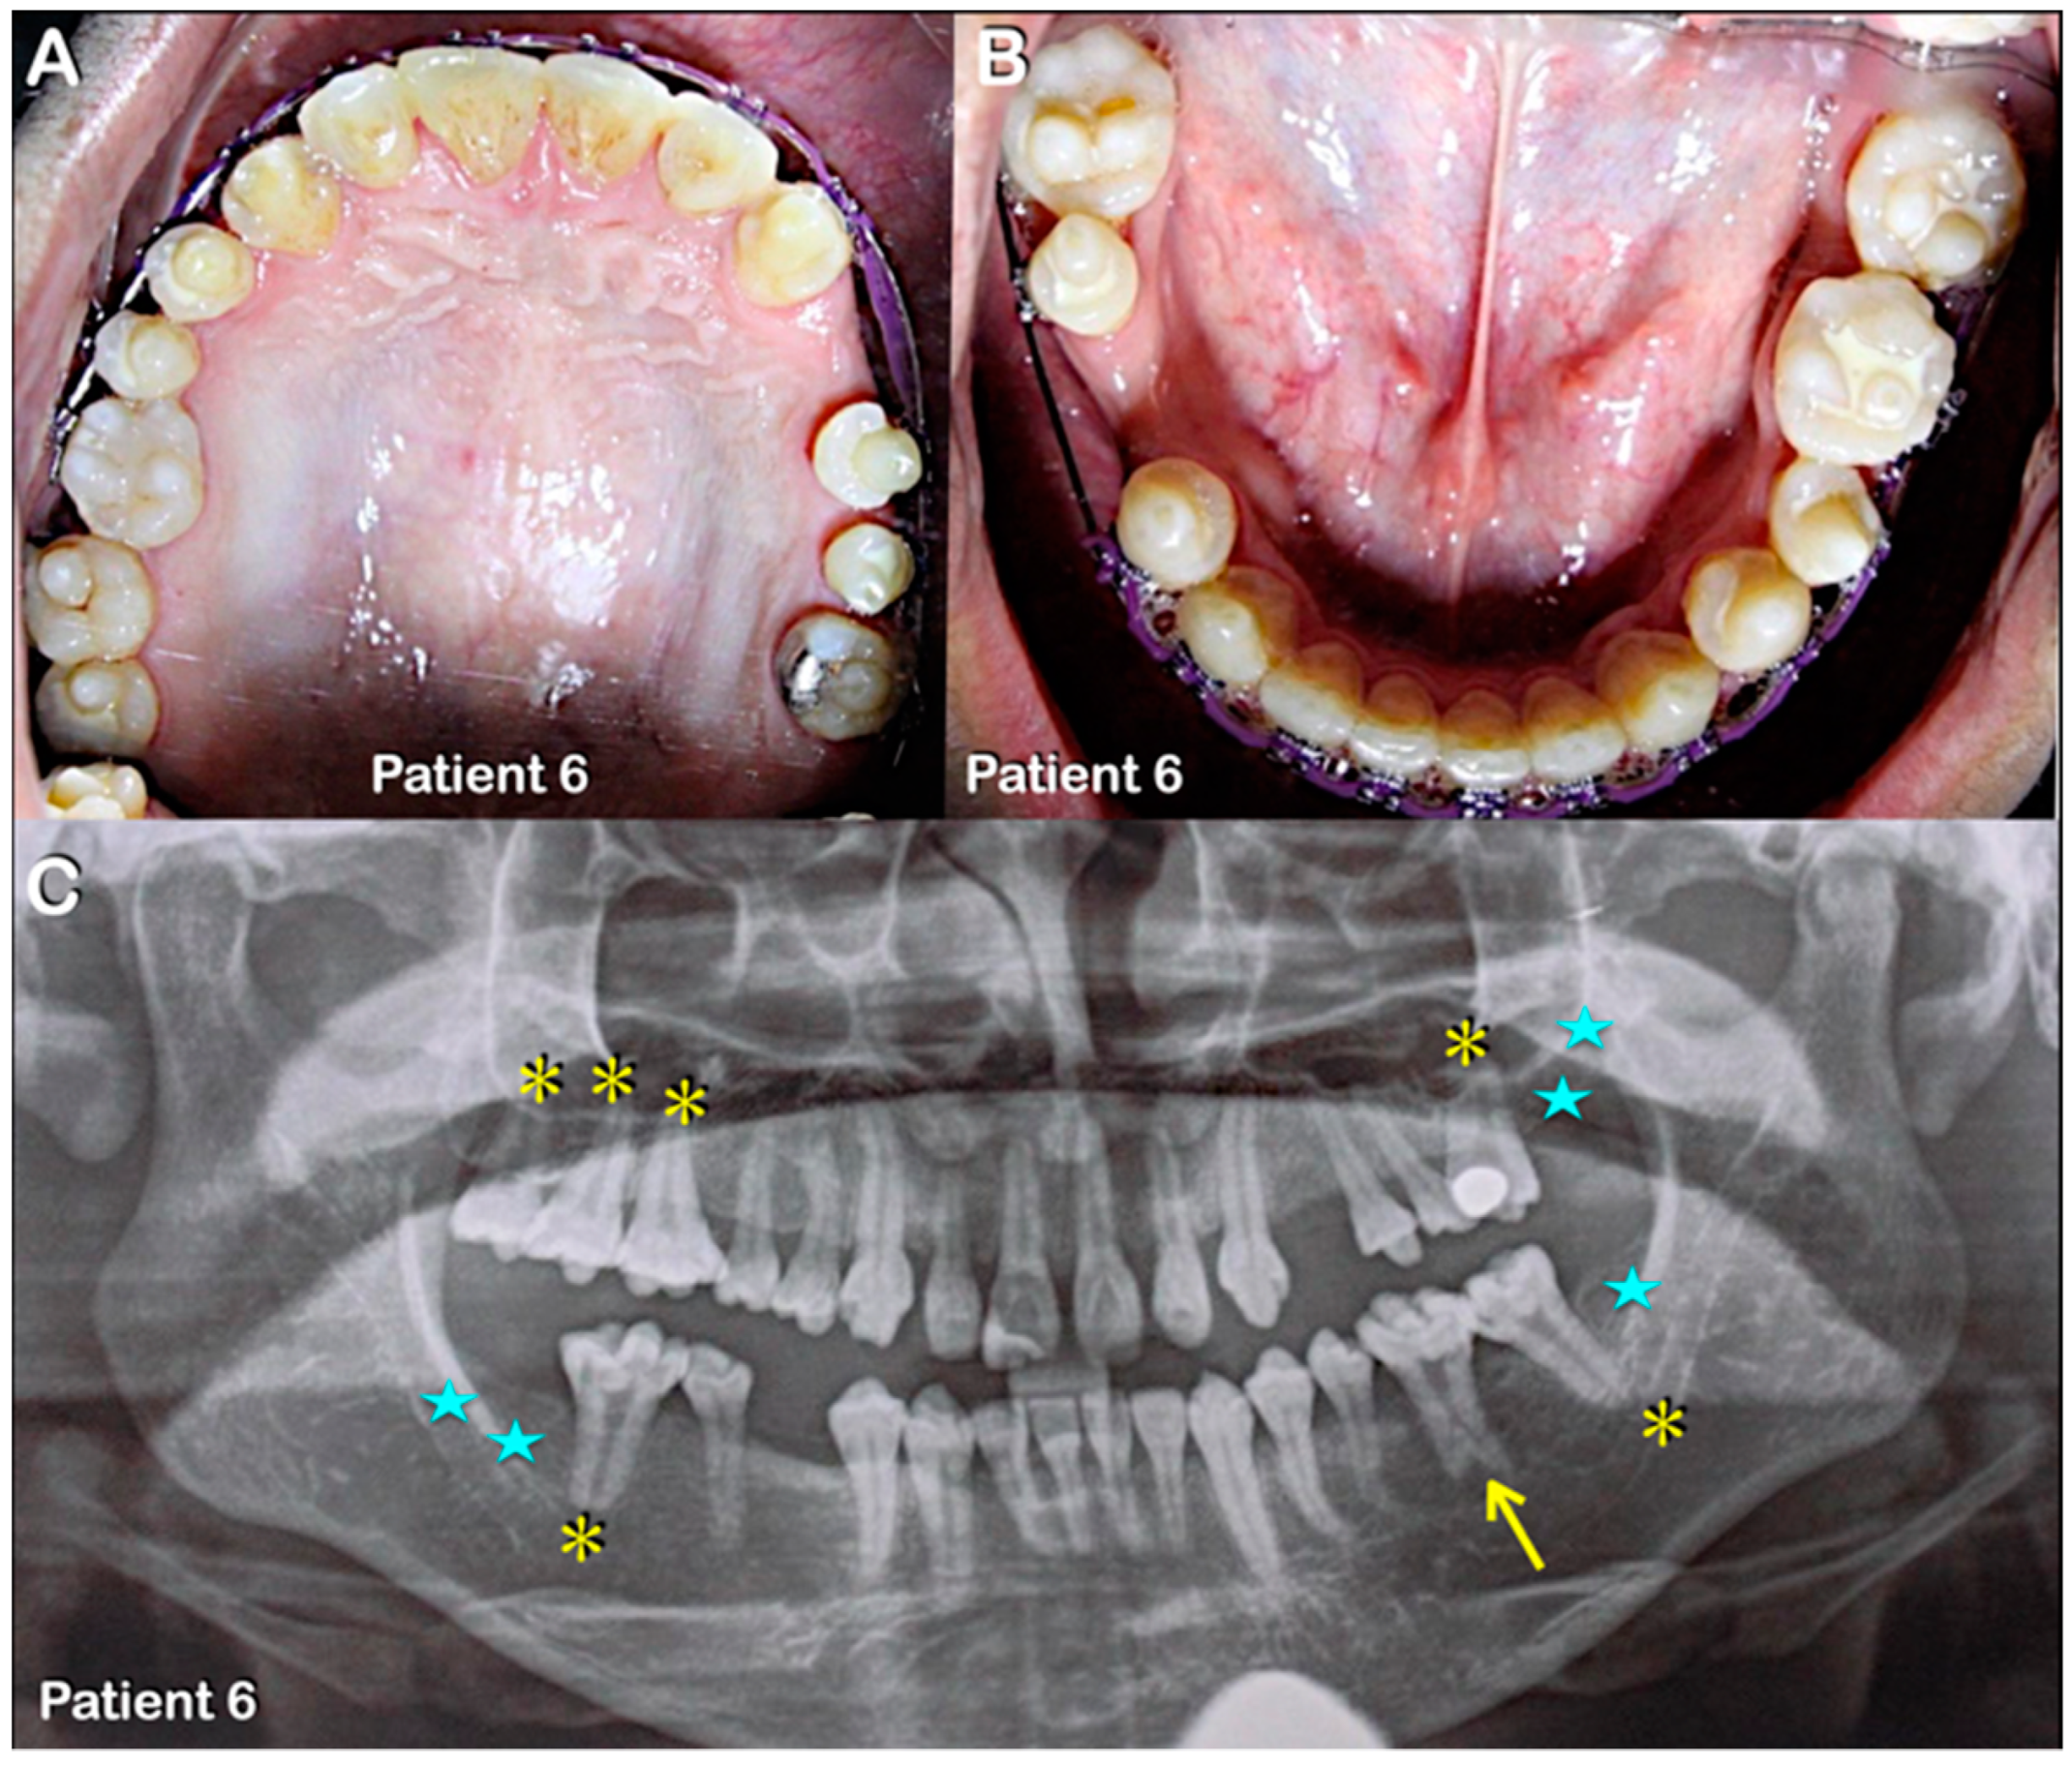

Figure 5.

Patient 6. (A–C) Patient 6. (A,B) Permanent dentition. Round-shaped permanent molars, molars with multiple supernumerary cusps, and premolars with single prominent cusps. (C) Panoramic radiograph showing agenesis of second and third permanent molars (blue stars) and single-rooted permanent molars (yellow asterisks). Note severe taurodontism (yellow arrow).